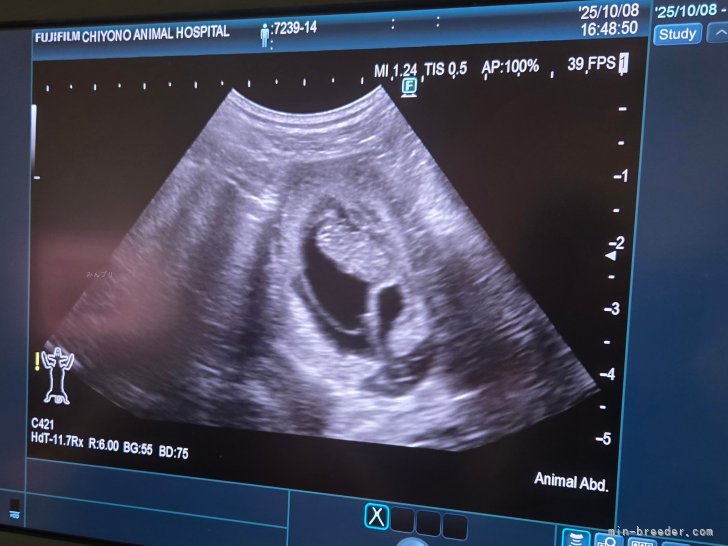

11月半ば頃出産予定です🫡🐾